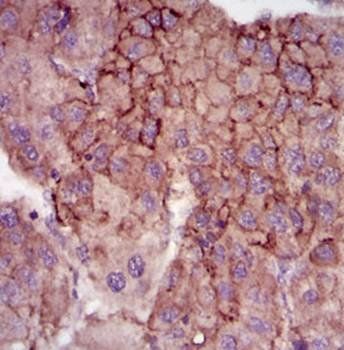

Immunohistochemical analysis of MELK staining in human lung cancer formalin fixed paraffin embedded tissue section. The section was pre-treated using heat mediated antigen retrieval with sodium citrate buffer (pH6.0). The section was then incubated with the antibody at room temperature and detected using an HRP conjugated compact polymer system. DAB was used as the chromogen. The section was then counterstained with haematoxylin and mounted with DPX.